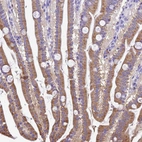

Immunohistochemical staining of human small intestine shows moderate cytoplasmic positivity in glandular cells.